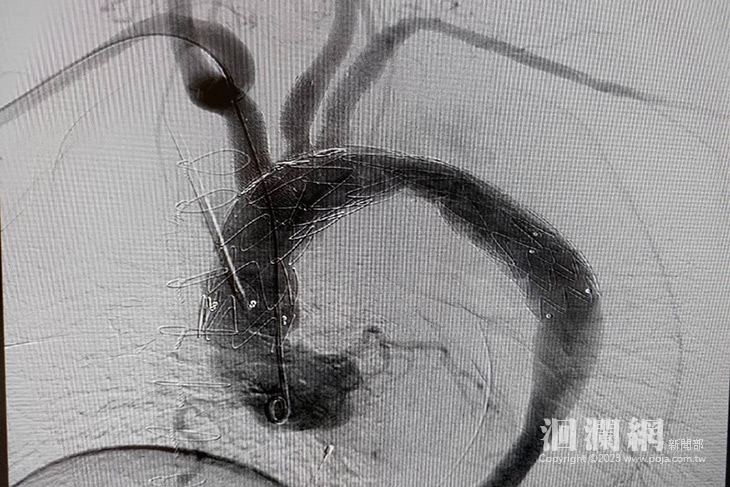

他說,手術過程主要是利用導管將支架放入主動脈弓所有分支中,並利用較大支架蓋住破口,讓血流順利從血管支架內經過。但這項手術難度較高,目前國內只有少數醫院有能力執行。